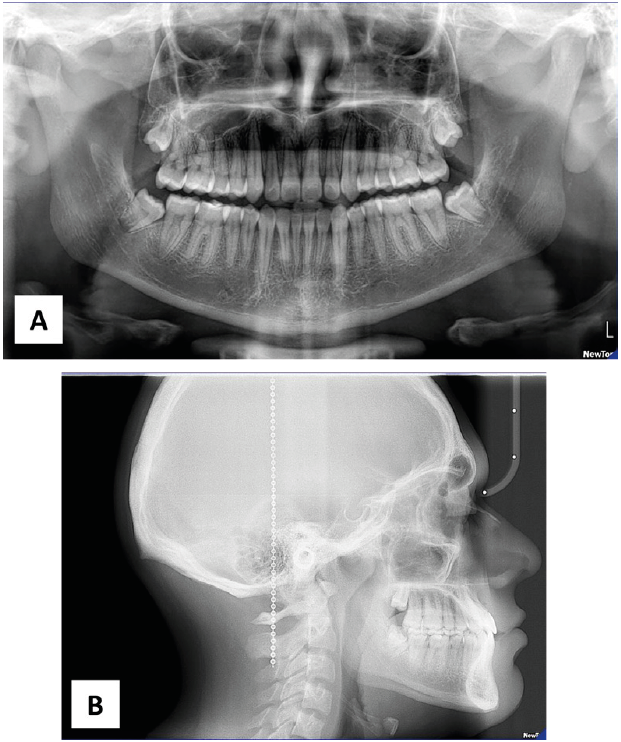

Paciente masculino de 12 años que asistió a la clínica de ortodoncia de la DEPeI de la Facultad de Odontología UNAM, donde tenemos sus registros fotográficos (Figura 1), radiológicos (Figura 2) y digitales (Figura 3). El diagnóstico facial consistió en un perfil cóncavo, proquelia inferior y biotipo euriprosopo. Cefalométricamente el paciente presentó Clase III esquelética combinada por retrusión y prognatismo, con un tipo de crecimiento horizontal (Figura 2.B). Dentalmente, clase III molar y canina bilateral y mordida cruzada anterior.

Figura 1 Imágenes iniciales. A. Fotografía extraoral frontal. B. Fotografía extraoral lateral. C. Fotografía intraoral en vista frontal. D. Fotografía intraoral en vista lateral derecha. E. Fotografía intraoral en vista lateral izquierda.